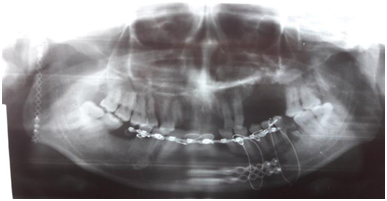

A 25-year old, male, patient presented with a comminuted mandibular fracture of the following areas: an Alveolar Fracture, Left; Parasymphyseal Fracture, Left; and a Condylar Neck Fracture, Right as shown in Figure 1. The patient complained of a gross deformity with malocclusion (Figure 2).

Figure 1 Pre-operative Panoramic X-ray showing a displaced right condyle on the left side of the picture.